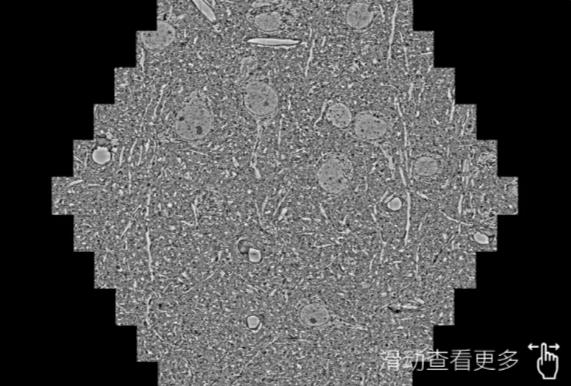

鼠脑切片。左图使用新余蔡司新余扫描电镜MultiSEM706对165μmx143pm面积区域成像,耗时仅需1.5秒。右图为鼠脑切片中30μm区域放大效果。样品由芝加哥大学B.Kasthuri提供。

使用蔡司高速新余扫描电镜MultiSEM对1mm²人脑皮层组织进行高分辨成像,并对其中的各种细胞结构进行三维重构分析。左图展示了2x3mm²组织平面中锥体神经元的三维重构效果。右图显示了局部体积神经元三维重构。图像由哈佛大学chtman实验室提供,渲染图由D. Berger 制作。